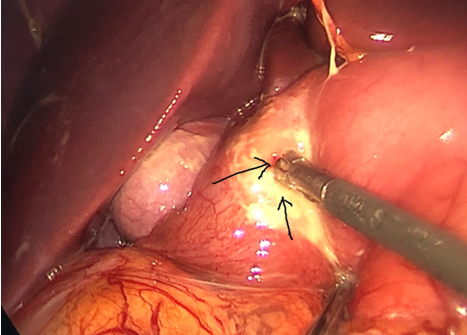

Trong quá trình phẫu thuật

nội soi quan sát thấy ổ bụng chứa nhiều dịch mủ bẩn, dịch tiêu hóa, phát hiện 1 lỗ thủng mặt

trước môn vị dạ

dày, bằng kinh nghiệm và tay nghề của bác sĩ phẫu thuật, bệnh nhân đã được khâu

đóng lỗ thủng, làm sạch ổ bụng.

Nội soi ổ bụng có nhiều mủ và giả mạc

Lỗ thủng dạ dày